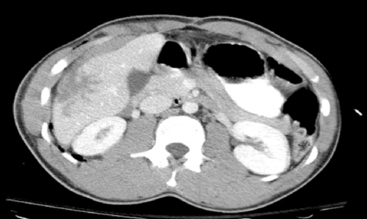

Pulmonary Contusion

A pulmonary contusion is a bruise on the lung resulting from lung parenchymal injury. Although a pulmonary contusion can be asymptomatic and diagnosed only on CT scan, it can cause respiratory compromise following major blunt chest trauma.13,44 A significant pulmonary contusion will cause hypoxemia, and opacification is visible on a chest radiograph or CT scan (see Figs. 19-3, B and 19-4).

image

Fig. 19-4 Pulmonary contusion on chest radiograph and computed tomography (CT) scan. A, Chest radiograph. Note the increased opacification in the patient’s right lower lung fields (arrows). Note the absence of rib fractures. B, CT scan from the same patient demonstrating opacification (white contusion is visible in the dark air density) of the right lower lung. The trachea is not visible in mediastinum, so opacification is below the area of bifurcation of the trachea into bronchi. This CT view is shot from below the area of contusion with a view in the cephalad direction. The patient’s right chest appears on the left side of this image, and the patient’s left chest is visible on the right side of this image. The front of the patient is the top of this image, and the patient’s back is at the bottom of this image; thus, the patient’s heart is anterior (visible as a white oval) and vertebral column is posterior.

An associated hemothorax typically suggests the presence of a more severe lung injury. Treatment includes supplementary oxygen and may require positive-pressure ventilation with oxygen support and positive end-expiratory pressure.